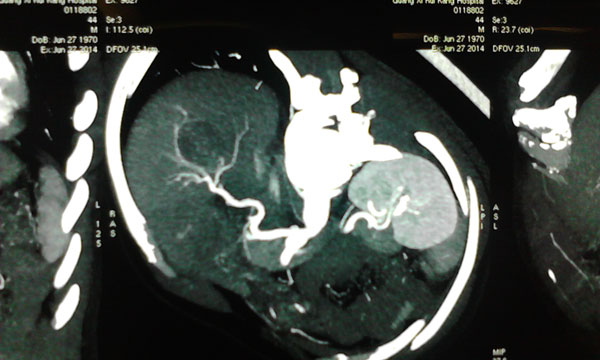

肿瘤与肝动脉